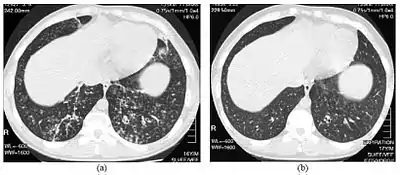

High-resolution computed tomography images of the lower chest in a 16-year-old boy with diffuse panbronchiolitis

High resolution computed tomography (HRCT) images of the lower chest in a 16-year-old boy initially diagnosed with DPB (left), and 8 weeks later (right) after a 6-week course of treatment with erythromycin. The bilateral bronchiectasis and prominent centri-lobular nodules with a "tree-in-bud" pattern shows noticeable improvement.